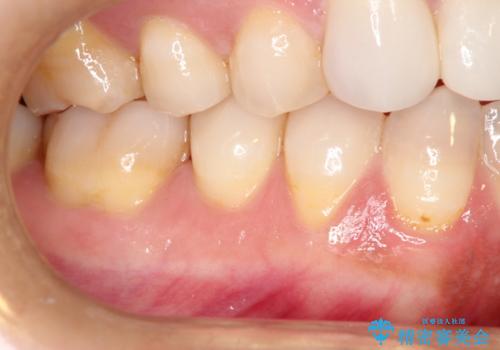

- 昔に受けた矯正治療がきっかけで歯肉が下がってしまった事を主訴として来院された患者様です。

結合組織移植術を行う方法を提案しましたが、傷口が口蓋にもできるのが嫌だとのことで、代替案としてバイオマテリアルを併用した根面被覆術を計画致しました。

治療対象部位は右下4,5,6番の3本です。